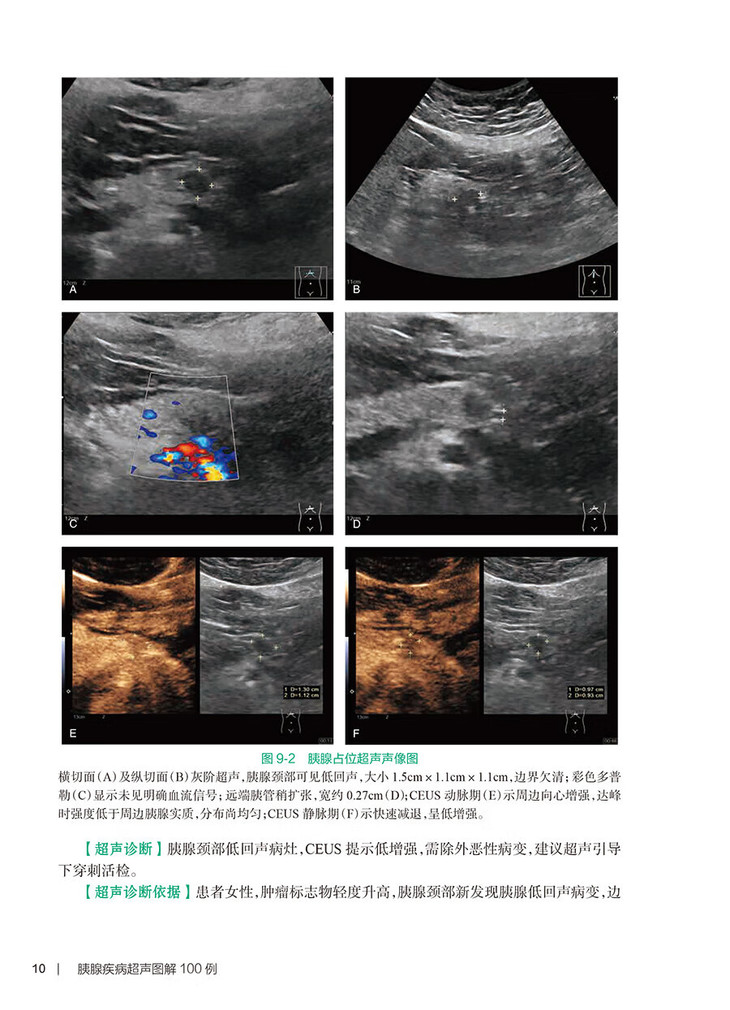

与PBL教学腹部超声部分相呼应,以100例典型图片入手,简明扼要,结合病史、临床表现,进行图像的分析说明。用大量图片,包括产前、儿童及成人胰腺病例,全面阐述胰腺相关疾病,在短期内实现广大超声住培生对胰腺疾病超声表现的深刻认知。100例胰腺经典疾病的灰阶、彩色多普勒、超声造影等图片并与其他影像学比较,包括产前、儿童及成人胰腺病例,生动形象,全面阐述胰腺疾病,帮助超声住培生和/或相关的临床医生迅速掌握疾病相关超声表现,提高超声诊断水平。